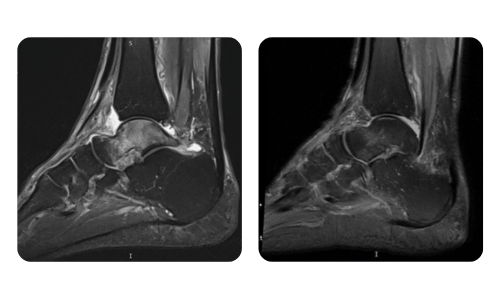

Progresul pacienților noștri, măsurat înainte și după terapia hiperbară, reflectă eficiența și impactul pozitiv al tratamentului. Descoperă rezultate documentate ale terapiei hiperbare la clinica Hyperbarium Oradea, bazate pe evaluări clinice și date obiective care evidențiază îmbunătățiri semnificative în diverse afecțiuni.